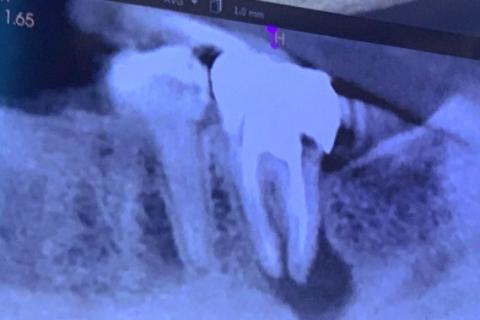

This dental X-ray shows a posterior tooth with previous root canal treatment. A clear radiolucent area at the root apex is visible, indicating a persistent or recurrent infection. The surrounding bone shows signs of loss consistent with chronic inflammation.

-

Root canal–treated tooth with dense coronal restoration

Apical radiolucency at the root tip

Loss of normal bone trabeculation

Widened periodontal ligament space

Infection appears chronic rather than acute